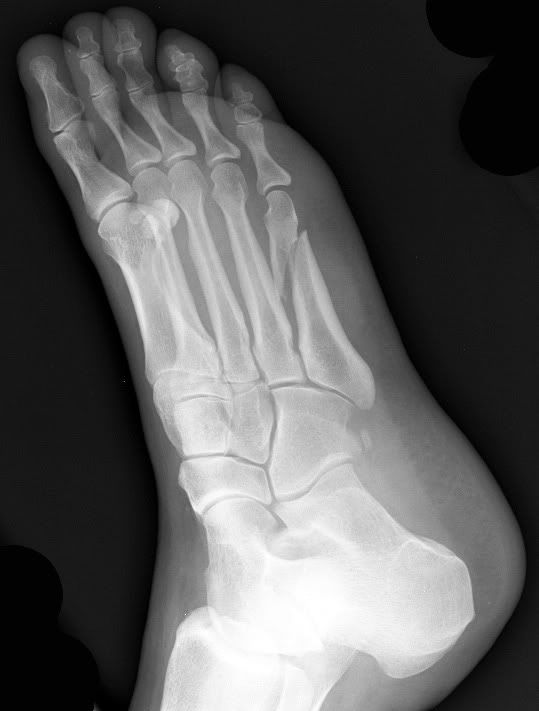

Metatarsal Fracture X Ray Views . Radiographs may be used to diagnose all acute fractures,. Caput ossis metatarsi, corpus ossis metarisi and the basis. Most metatarsal shaft fractures are oblique or transverse (figure 1a). Displacement is usually minimal unless more than one metatarsal is fractured. Radiography is the first and often the only investigation required for the diagnosis of fractures. Still, subtle injuries may be missed and require further imaging such as ct, mri or radiographic. Fractures of the 5th metatarsal base are a. Metatarsal fractures are usually easily recognised, but are often only visible on one view. Every metatarsal bone consists out of three parts: Metatarsal fractures are among the most common injuries of the foot that may occur due to trauma or repetitive microstress. The foot consists out of 5 metatarsal bones per foot. The biomechanics of the fractures differ as do their natural history and treatment, therefore an understanding of these entities is. These injuries are well demonstrated on the standard views of the foot.

Metatarsal fractures are usually easily recognised, but are often only visible on one view. Every metatarsal bone consists out of three parts: Still, subtle injuries may be missed and require further imaging such as ct, mri or radiographic. Fractures of the 5th metatarsal base are a. Displacement is usually minimal unless more than one metatarsal is fractured. Metatarsal fractures are among the most common injuries of the foot that may occur due to trauma or repetitive microstress. The foot consists out of 5 metatarsal bones per foot. Caput ossis metatarsi, corpus ossis metarisi and the basis. Radiographs may be used to diagnose all acute fractures,. Most metatarsal shaft fractures are oblique or transverse (figure 1a).